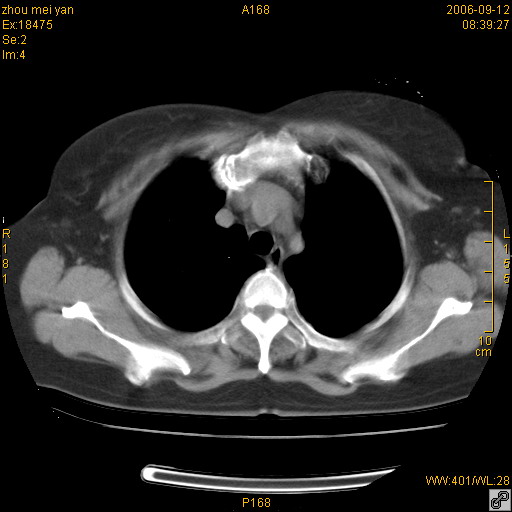

患者、女、55岁。因心率失常住院检查ct发现胸部多发结节。腹部b超肝、胆、胰、脾、肾、子宫附件未见异常。无结核病史,无粉尘接触史。请大家来会诊。谢谢!

病变位于胸膜,多发结节,边界清楚,内见小结节状钙化。其它未见异常。

双侧胸膜多发结节,形态不规则,边缘较清楚,每一个结节中心似乎都有钙化点的特征,与胸膜广基相切。临床无结核病史,无粉尘接触史。

胸膜间皮瘤可能性大。在气管隆突前可见一肿大淋巴结影。

影像表现十分有特点:双侧肋胸膜及膈胸膜广泛散在分布大小在2至6mm左右,较大病灶中心可见钙化。

考虑恶性胸膜间皮瘤可能性大,病灶位于胸膜,以宽基地与胸膜相连,呈结节样改变,部分病灶内可见点状钙化影。请各位老师多多指导!

双侧肋胸膜及膈胸膜广泛散在分布大小不等结节影,较大病灶中心可见钙化。